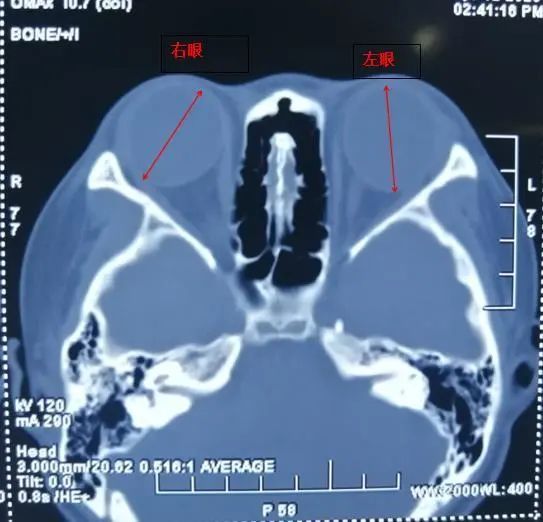

如果能早点做这件事,这对双胞胎姐妹也许不会有2600度的高度近视u2026_腾讯新闻